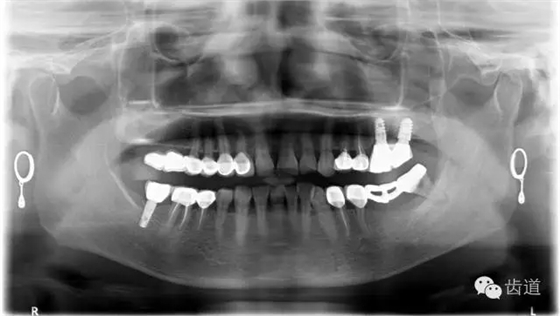

1、術(shù)前全景片

2、45,46術(shù)前片顯示根管上段充填物,根管影像不清晰,少許根尖暗影

3、34術(shù)前片顯示遠中面暗影近髓

4、 全景片